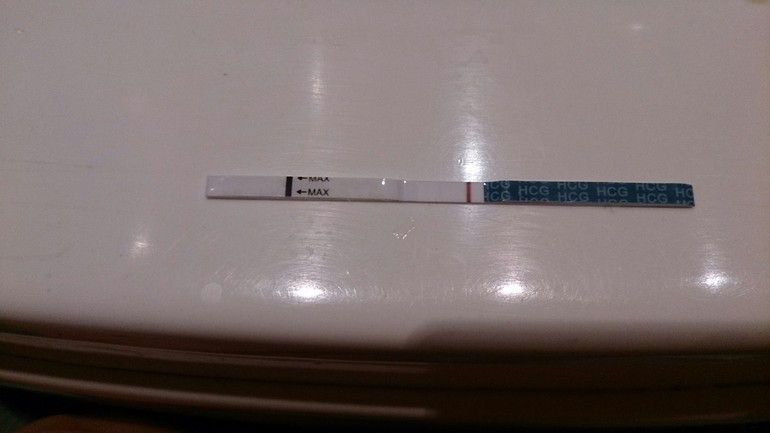

Сил, терпения и только положительных результатов! Мы за вас очень переживаем и крепко зажав кулачки ждем полосатые тестики и трехзначные ХГЧ!